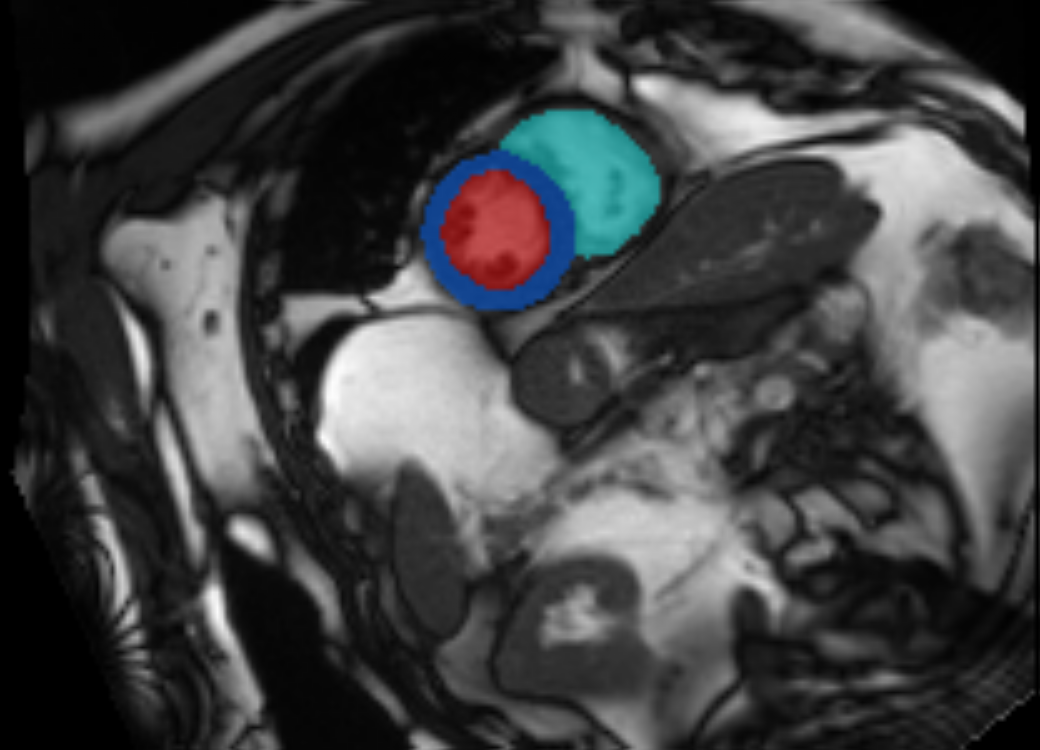

Our CUSSP method consists of five main steps, shown in Figure 4, with the first two steps representing data preprocessing, and the later three steps using network components trained for MR classification, as described in the next section. The pre-processing of the CMR imaging sequence is shown in Figure 8 in the Appendix. We used the segmentation model in 2.1 to locate the mitral valve and the orientation of the left ventricle. We then cropped a square patch with the mitral valve at its center positioned horizontally. After cropping, we applied histogram equalization to the patch with the pixel intensity range of the left atrium. The resulting patches are used by the downstream networks.

Refer to caption

Figure 8: Detailed overview of the pre-processing steps for CUSSP. Top: Example of the 4CH CMR images in the original contrast (left), the left atrium histogram equalized contrast (middle), and the cropped patch histogram equalized contrast (right), with blue contours outline the left atrium, and the red square boxes outline the patch to crop. Bottom: Example of the cropped mitral valve patch as outlined in the red square boxes in the top row.